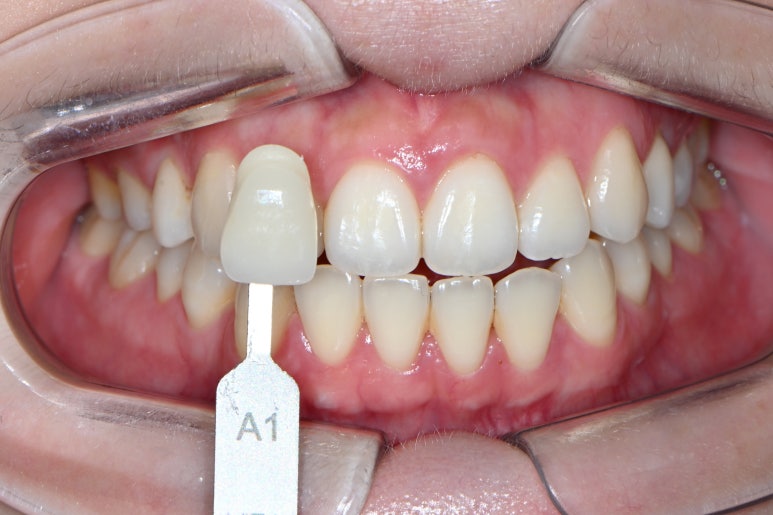

치아 미백을 받으러 오신 분들은 이렇게 치아 색상표를 함께 두고 상담을 합니다.

보통 한국사람 치아는 A1,A2,A3,A3.5 등등 A계열의 색상이 많은 것 같아요~

참고로 숫자가 클수록 치아는 어두워집니다.

마치 A1 처럼 보이는 색상....

사실 더 밝아질 것은 없다고 생각하지만, 이런 경우 치아미백을 하면 노란색 끼가 없어지면서 더 블루한 느낌이 되는 원리로 밝아져 보이는 효과를 얻게 됩니다.